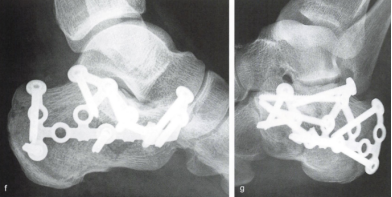

按照以往常规的治疗策略来看,少部分未累及关节面或跟骨高度、宽度无明显变化等的简单骨折可选择保守治疗(手法整复及石膏固定制动)。而大部分累积关节面或骨折碎裂、移位明显的跟骨骨折常常需手术治疗,否则患者后期很可能会面临创伤性关节炎、跟骨畸形愈合致创伤性扁平足等风险,从而导致患者出现长期跟部疼痛、穿鞋及行走困难等不良后果,严重影响患者日常生活及工作等。其中,对于关节面严重碎裂移位的复杂跟骨骨折,目前标准的手术方式是通过足跟外侧作一长“L”形皮肤切口行切开复位钢板螺钉内固定术。其优势在于暴露充分,直视下复位,复位效果好,远期并发创伤性关节炎及骨折畸形愈合风险相对较低。

在骨科中心主任吴超的带领下,团队采用了天玑Ⅱ骨科手术机器人为程某开展了微创手术治疗,该手术时间短、创伤小、出血少、透视次数少,同时实现了骨折块的解剖复位和精准的螺钉置入及固定;术后影像学显示患者关节面完全复位,螺钉位置良好,固定可靠。